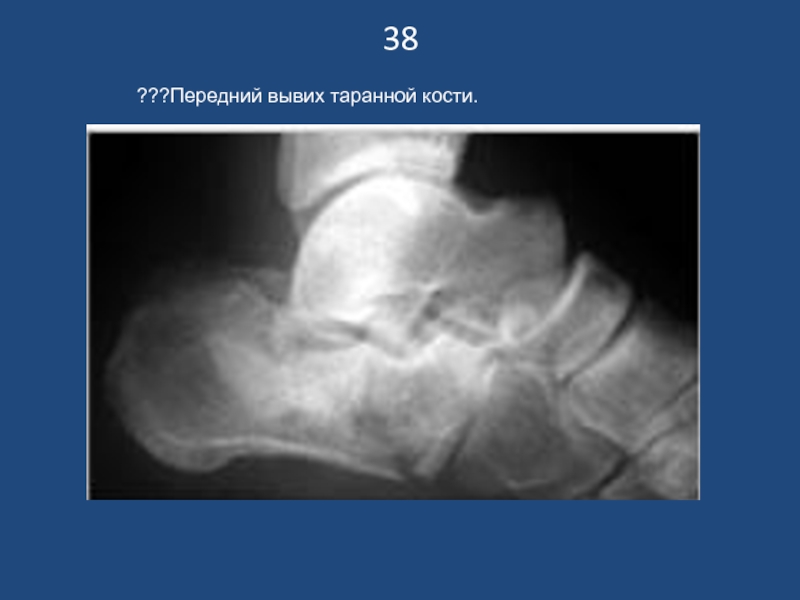

???Передний вывих таранной кости.

38???Передний вывих таранной кости.